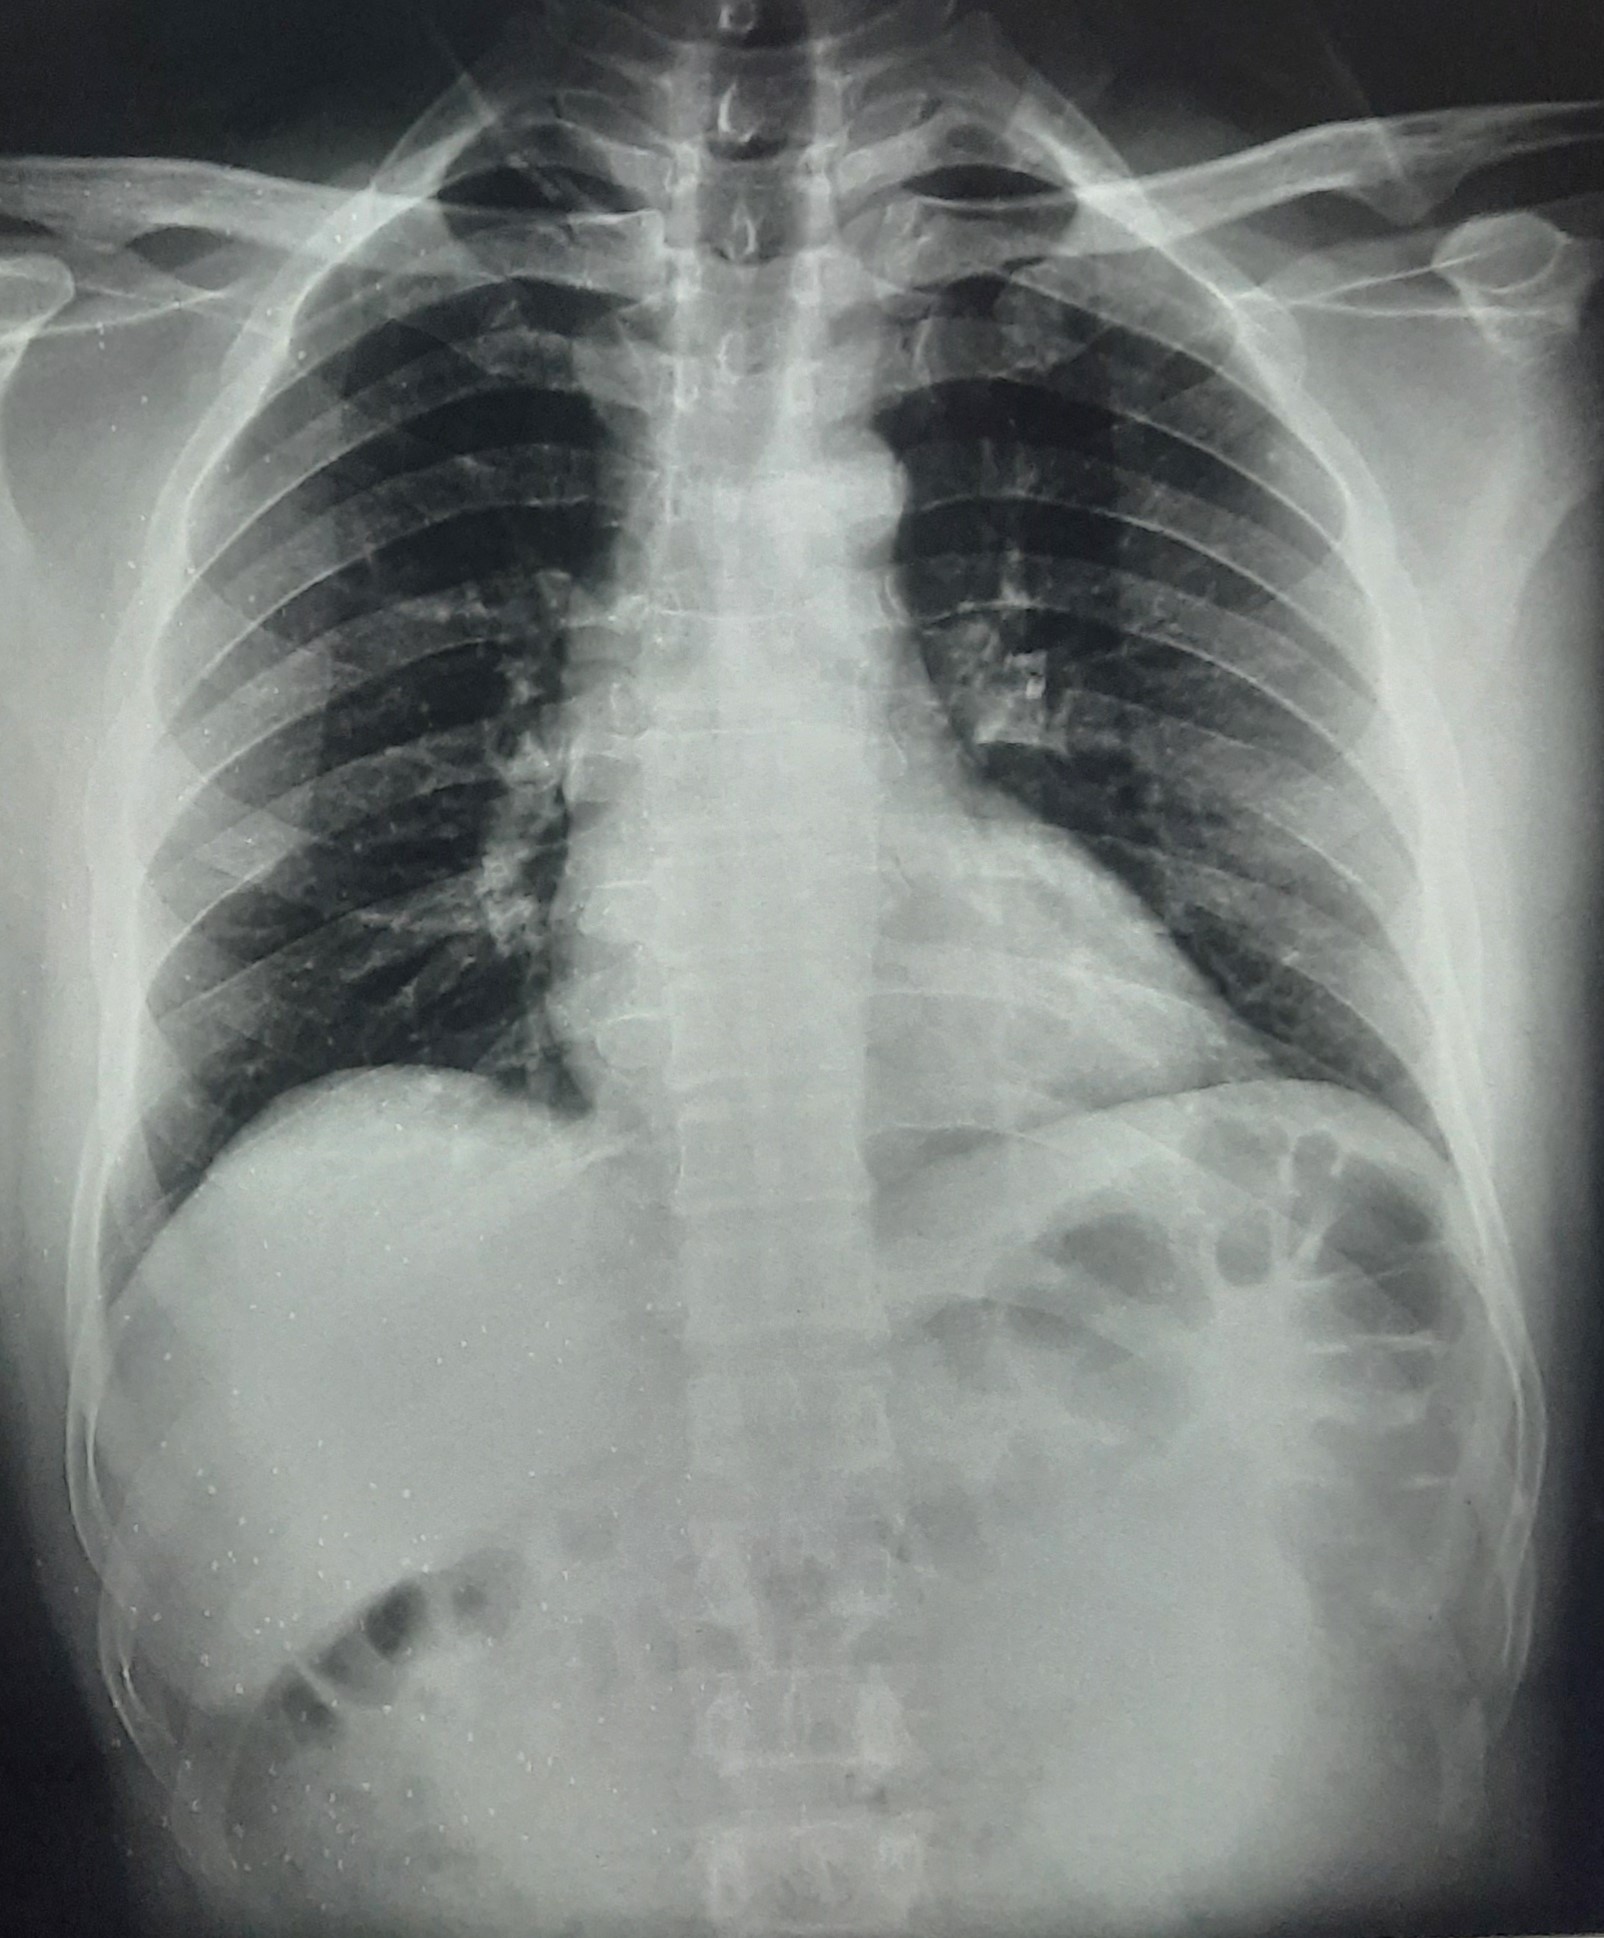

| 322 | IGGMC, Nagpur, Nagpur | P2 | 29-4150 | Ramsaloni Tripati | Consent taken on Paper | 80 Yrs. |

Provisional Diag : COPD in infective Exacerbation in current smoker with systematic HTN

Final Diag : COPD in infective Exacerbation in current smoker with systematic HTN |

Non-TB Case (Confirmed) | Abnormality visible on x-ray |